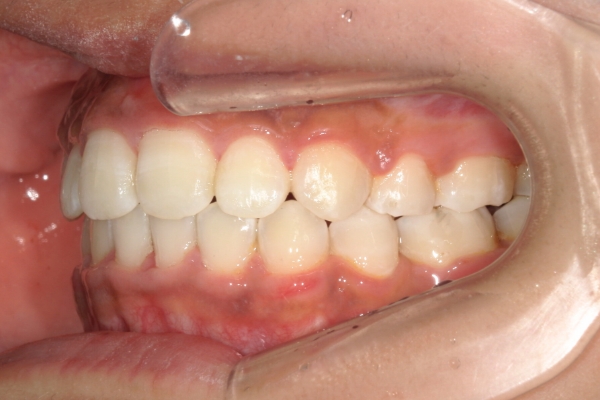

BEFORE

治療前

AFTER

治療後

上顎前歯が1cm近く前方に出ており、叢生を改善しつつ前歯を大きく引っ込めるために上下顎小臼歯の抜歯が必要と診断しました。治療後は、主訴であった前歯の突出と奥歯の噛み合わせのずれが改善され、上下の咬合関係が安定しました。